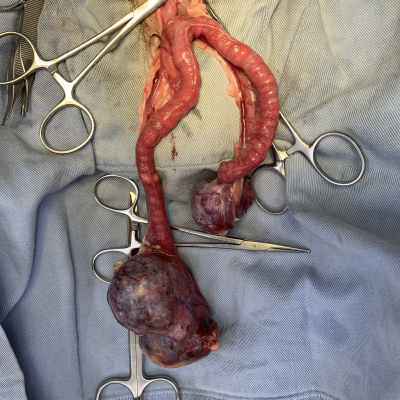

卵巣腫瘍

15歳の小型犬でみられた症例です。

【症状】

元気食欲がなくなり動かなくなったので来院しました。

【診断】

身体検査では熱や聴診などは問題ありませんでしたが、触診で腹部に腫瘤を触知したため超音波検査とX線検査を実施したところ腹腔内の腫瘤を確認、

血液検査には異常がないため腫瘤からの痛みが原因と考えられました。

【治療】

内科治療より外科治療が適切であり、血液検査等から手術は可能と診断し飼主様と相談の上手術を実施しました。

開腹したところ、病巣は卵巣であったが他の臓器との癒着はなかった(写真参照)ため、卵巣と子宮を切除して手術を終了しました。

【術後】

三日後に元気食欲が正常にもどりました。

【腫瘍の検査結果】

腺癌:リンパ管や血管から腫瘍細胞は認められないことから転移の可能性は低いと診断されました。